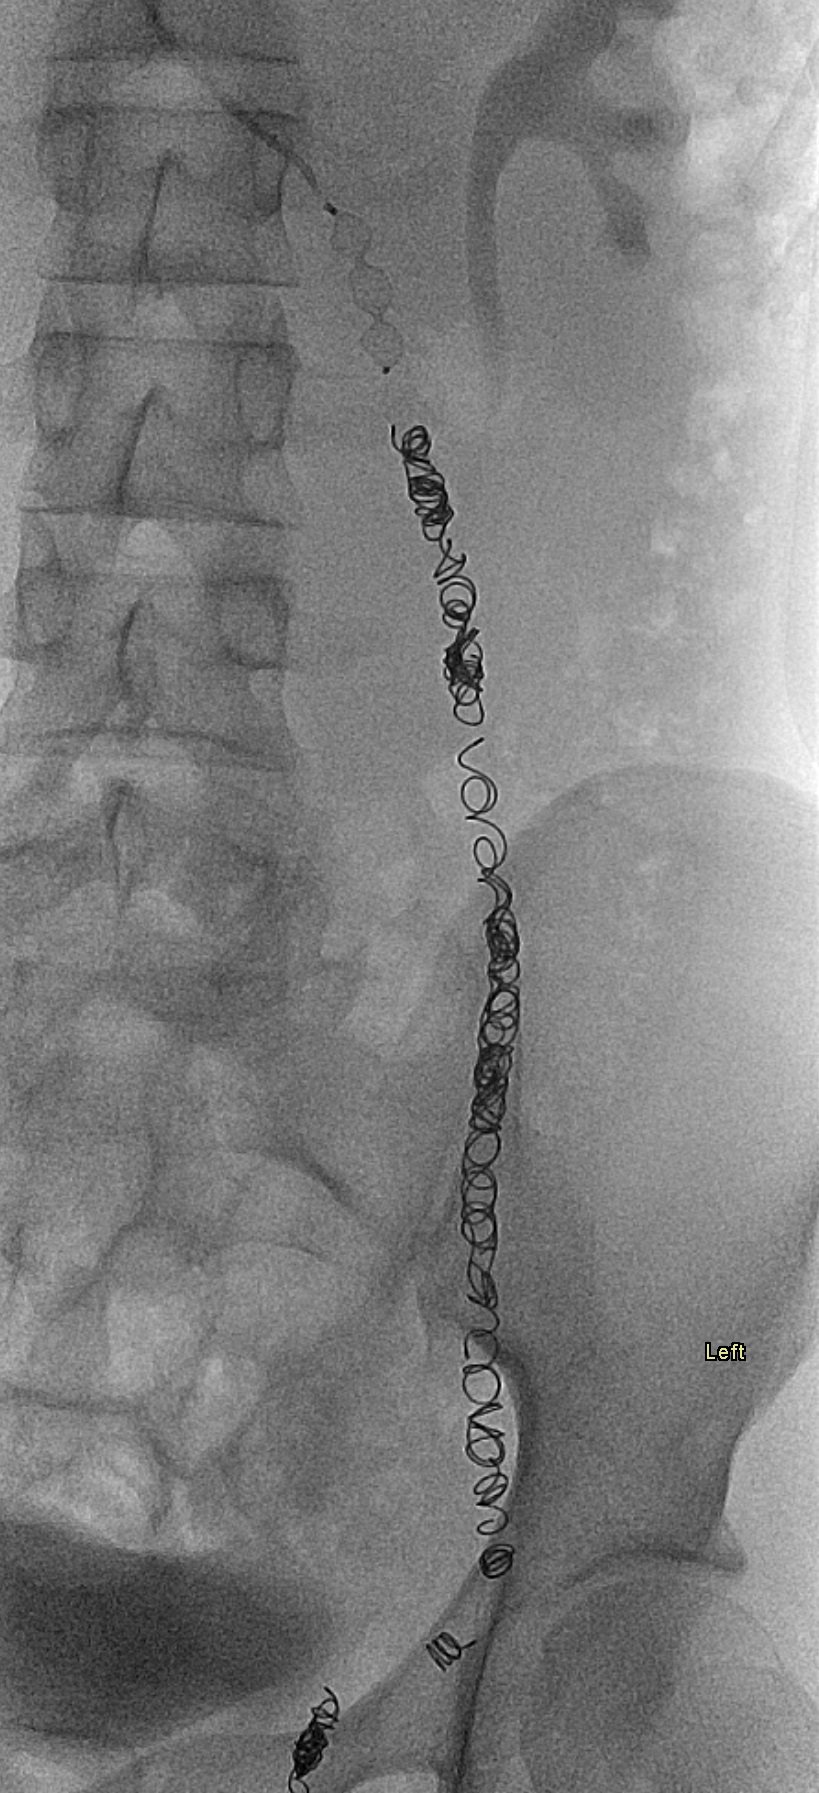

17-year-old male with a long history of left-sided varicoceles status post surgical ligation in 2015 presents with recurrence of symptoms, referred to us for left gonadal vein embolization.

Ultrasound demonstrates enlarged veins (>3 mm) adjacent to the testicle. Angiogram demonstrates reflux of contrast into the left gonadal vein to the level of the scrotum, indicating venous valvular incompetence. Coil embolization and sotradecol sclerotherapy of the left gonadal vein were performed, with an Amplatzer plug at the top of the vein. Repeat angiogram demonstrates no contrast opacification of the vein. Red arrows indicate the left gonadal vein and the blue arrows indicate the left renal vein.